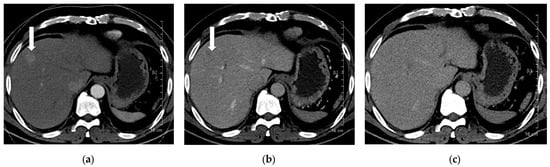

A total of 168 focal liver lesions were identified in 93 participants (80 lesions in the high-concentration iodine group [n = 47] and 88 lesions in the low-concentration iodine group [n = 46]). Lesions comprised HCCs (n = 80), adenocarcinomas (n = 14), dysplastic nodules (n = 15), hemangiomas (n = 33), and regenerative nodules (n = 3). Lesion size was equivalent between the high- and low-concentration iodine groups (14.36 ± 14.72 mm versus 17.50 ± 12.27 mm, p = 0.134). Per-lesion detectability showed no significant difference between the groups (0.862 versus 0.909, p = 0.18; Table 6). Among detected lesions, the mean conspicuity score was significantly higher in the LCIC group than in the HCIC group (4.41 versus 4.07, p = 0.002) (Figure 3, Figure 4, Figure 5 and Figure 6).

Figure 3. A 66-year-old man with hepatocellular carcinoma (HCC). CT was performed using high-concentration iodine contrast material (total iodine dose, 677.82 mg I/kg). Overall image quality in the arterial and portal phases was acceptable (mean scores more than 4): (a) A 15-mm enhancing nodule (arrow) is visible on the arterial phase at 120 kVp; (b) The nodule is inconspicuous on the portal phase; (c) Washout is evident on the delayed phase (arrow). Both reviewers diagnosed the lesion as HCC.